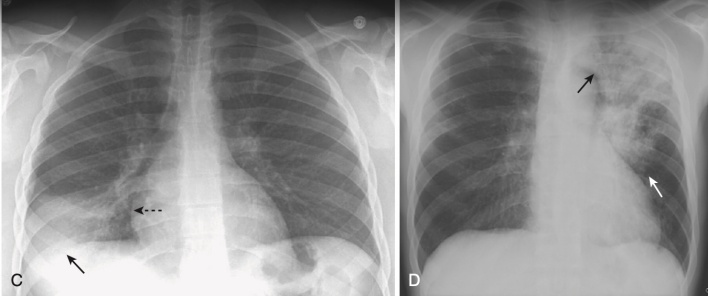

- Vi sinh vật nguyên mẫu gây ra viêm phổi hang là vi khuẩn lao (Mycobacterium tuberculosis).

- Tạo hang thường gặp trong lao hậu tiên phát (lao tái hoạt) nhưng hiếm gặp ở lao nguyên phát. Các hang thường nằm ở các thùy trên, hai bên và có thành mỏng, bờ trong nhẵn và không chứa mức dịch – khí (Hình 7). Sự lây lan xuyên phế quản (từ một thùy trên sang thùy dưới bên đối diện hoặc đến một thùy khác trong phổi) sẽ khiến bạn nghĩ đến nhiễm khuẩn Mycobacterium tuberculosis.

- Các tác nhân truyền nhiễm khác gây ra viêm phổi hang là:

- Viêm phổi do tụ cầu có thể tạo hang và tạo ra các túi khí (pneumatoceles) có thành mỏng.

- Viêm phổi do liên cầu, viêm phổi do Klebsiella, và bệnh do coccidioidomycosis cũng có thể gây viêm phổi hang.